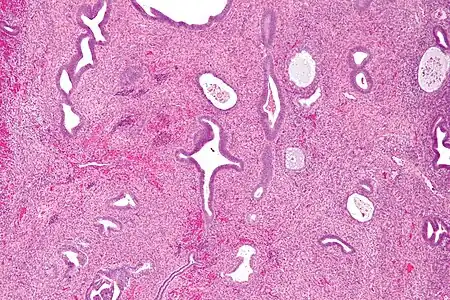

Pathology

Endometrial polyps can be solitary or occur with others.[12] They are round or oval and measure between a few millimeters and several centimeters in diameter.[7][12] They are usually the same red/brown color of the surrounding endometrium although large ones can appear to be a darker red.[7] The polyps consist of dense, fibrous tissue (stroma), blood vessels and glandlike spaces lined with endometrial epithelium.[7] If they are pedunculated, they are attached by a thin stalk (pedicle). If they are sessile, they are connected by a flat base to the uterine wall.[12] Pedunculated polyps are more common than sessile ones.[11]

Micrograph of an endometrial polyp. H&E stain -

Myometrium (smooth muscle cells) versus endometrial stroma (more cellular) versus endometrial polyp stroma (more collagenous). H&E stain